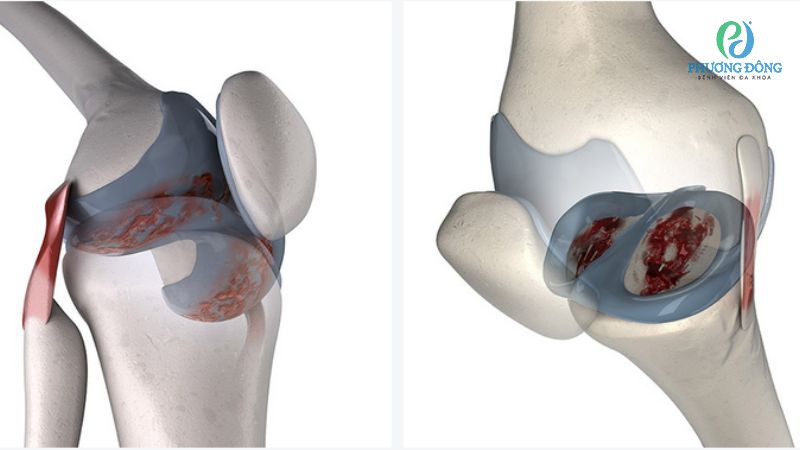

Viêm màng hoạt dịch

Viêm màng hoạt dịch xuất hiện khi các khớp trên cơ thể liên tục xảy ra tình trạng viêm, khiến dịch nhầy hoạt dịch phải sản xuất liên tục để thực hiện chức năng bảo vệ. Bệnh có thể tự diễn biến, chuyển nặng nếu không được can thiệp y khoa sớm và kịp thời.

Bệnh lý viêm màng hoạt dịch có thể chuyển biến nặng nếu không được điều trị kịp thời

Khi chất nhầy dịch khớp bị viêm, suy giảm chức năng sẽ dẫn tới những hệ lụy nghiêm trọng lên sụn, xương, tổ chức dưới sụn. Bệnh nhân khi này đối mặt với nguy cơ giảm chức năng vận động, thậm chí yếu cơ hoặc bại liệt.